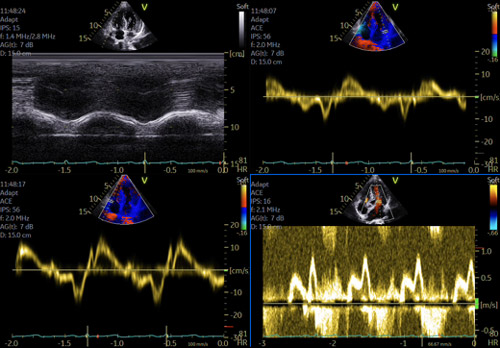

- Étude du strain atrial gauche, qui, < 13 % pendant la systole ventriculaire (phase réservoir), est aussi un facteur pronostique majeur, corrélé à la sévérité des symptômes, au risque thrombo-embolique, et à l’apparition d’arythmies atriales (Figure 4)4,5.

Figure 4 : Amylose TTR sauvage, 75 ans: en FA avec un DTI très altéré (s’ et e’ < 6 cm/s). Strain atrial < 20% mais non totalement effondré dans ce cas